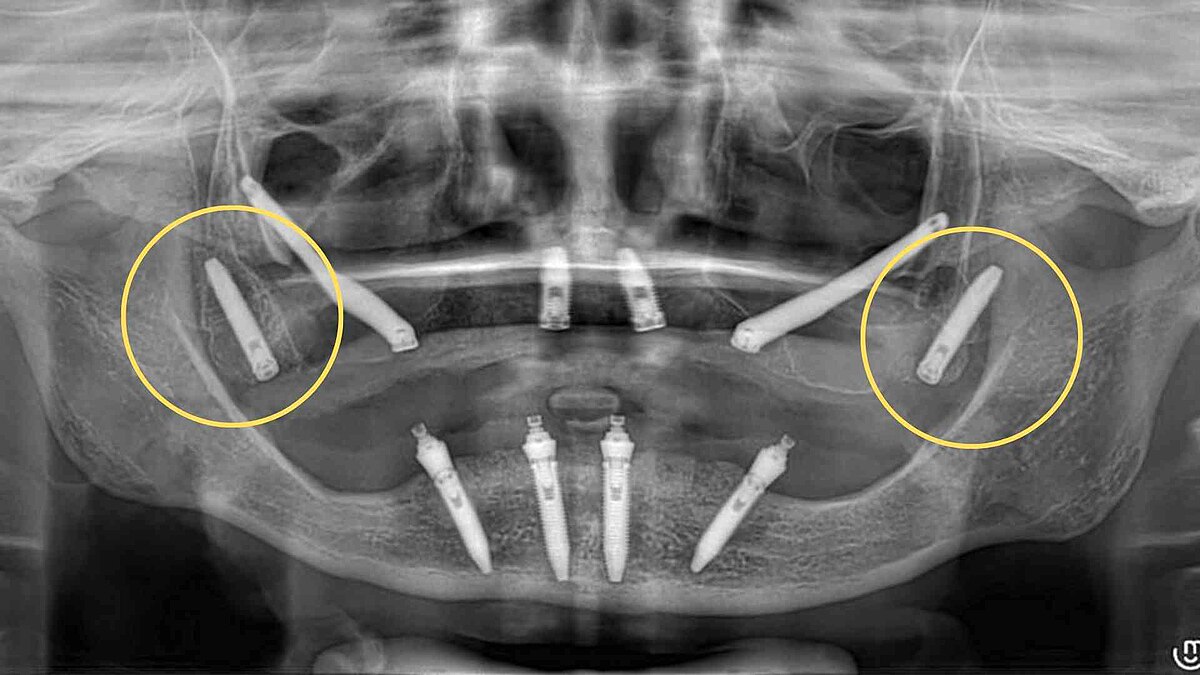

L’implantologia moderna ha fatto enormi progressi e, in casi di grave atrofia mascellare, una delle soluzioni più all’avanguardia è rappresentata dagli impianti pterigoidei. Questi dispositivi vengono posizionati nella porzione posteriore del mascellare, ancorandosi sull’osso pterigoideo del cranio, garantendo una stabilità eccezionale anche in assenza di massa ossea tradizionale.

Il ruolo del Sistema Smart Implant nel protocollo pterigoideo

Grazie alla tecnologia digitale 3D integrata nel Sistema Smart Implant dello Studio Amoruso, ogni fase dell’intervento è pianificata con precisione millimetrica.

L’inserimento degli impianti pterigoidei avviene tramite una procedura mini-invasiva, ottimizzata per garantire comfort e sicurezza, anche nei casi più complessi.